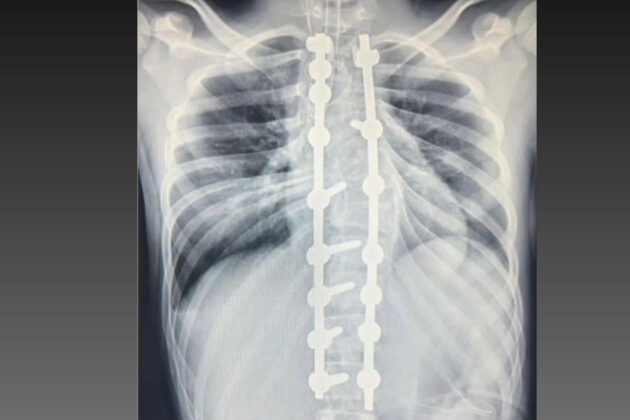

Aos 13 anos, Laura Dzwielewski Menegaz sonhava em voltar a montar a cavalo sem sentir dor. Diagnosticada com escoliose, ela passou por uma cirurgia de correção da coluna no Complexo Hospitalar do Trabalhador, em Curitiba. Antes do procedimento, atividades cotidianas eram acompanhadas por dores constantes e limitações físicas.

Casos como o dela são atendidos pelo Departamento de Deformidades Pediátricas da Coluna Vertebral, implantado em 2023, que se tornou referência no tratamento de escoliose em crianças e adolescentes. Desde então, mais de 200 cirurgias foram realizadas, além de tratamentos conservadores, como fisioterapia e uso de coletes ortopédicos.